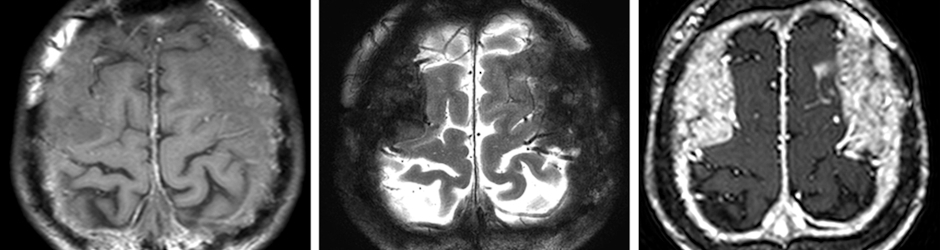

Pineal Region Tumor